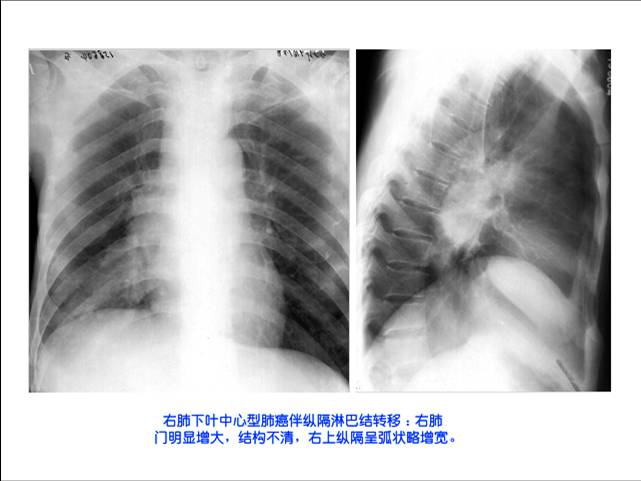

照片名称:右肺下中心型肺癌伴纵膈淋巴结转